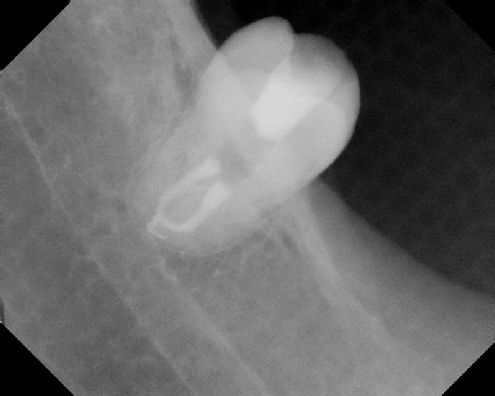

To view radiographic examples of the various types of root canal

cases we routinely treat, click on any of the categories shown below.

COMPLICATED ANATOMY LARGE LESIONS CALCIFIED CANALS PERFORATION / RESORPTION SEPARATED INSTRUMENTS SURGICAL CASES RETREATMENT / pOST REMOVAL OPEN APICES ACCESS THRU CROWNS Root Canal Case Portfolio Root Canal Specialists - Joel B. Chasen DMD, Joshua Dembsky DMD, Elinor Alon DMD, Shimona Malik DMD

Root Canal Anatomy - Meriden root canal anatomy - Meriden